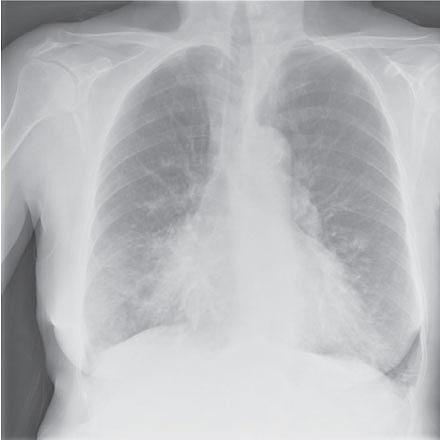

da TORCH-studiet blev lavet, og derfor opstillede man ingen prospektiv definition af pneumoni i hverken dette studie [6] eller samtidige studier. Fra en mere detaljeret gennemgang af pneumonier i TORCH-studiet fremgår det, at verifikation med røntgen af thorax langtfra forelå hos alle, end ikke hos patienter, der var indlagt med pneumoni [13]. Kun i et enkelt af de foreliggende studier opstillede man en prospektiv definition af pneumoni før studiestart. I studiet blev diagnosen verificeret ved billeddiagnostisk undersøgelse < 48 timer efter, at mistanken var rejst. Dette ændrede ikke den relative risiko for pneumoni ved behandling med inhalationssteroid [10]. Det er naturligvis problematisk, at definitionen af pneumoni ikke var standardiseret i studierne, idet KOL-eksacerbationer kan være blevet noteret som pneumoni og omvendt. I de fleste studier er pneumonier talt med som eksacerbationer, da en pneumoni uvægerligt fører til flere lungesymptomer og behandles med antibiotika. I TORCH-studiet udgjorde forværringer, der blev kategoriseret som pneumoni, 7% af alle eksacerbationer [13]. Studierne varierer i længde, og et enkelt af dem varede kun i 26 uger [9].